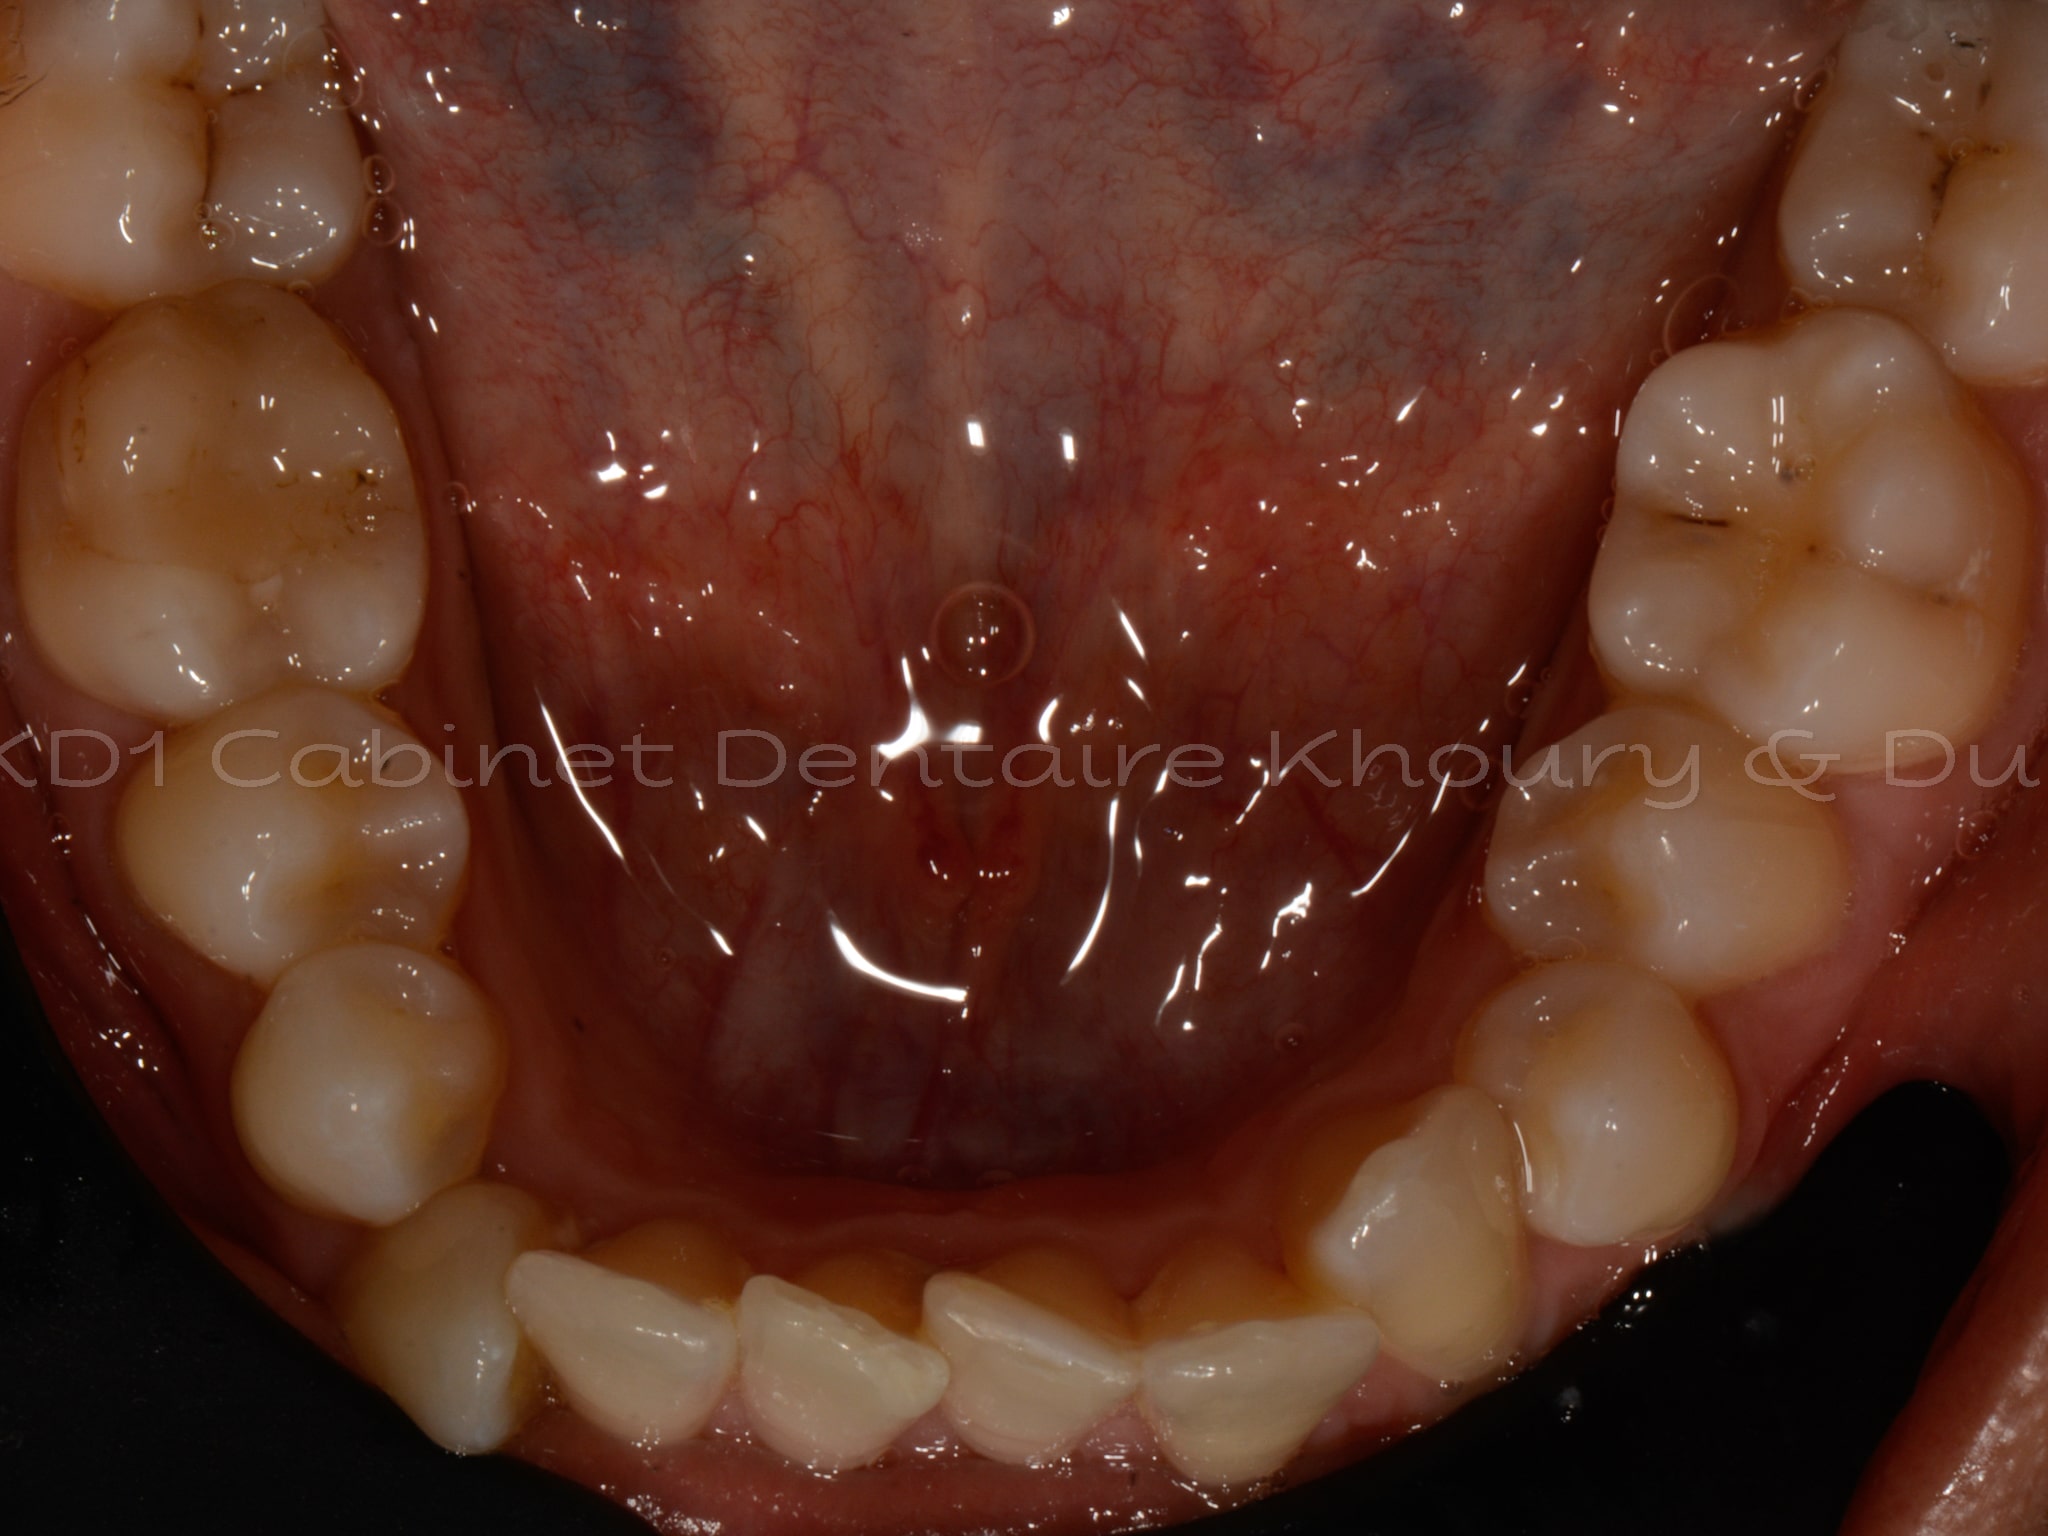

Cas #1 – Traitement avec des bagues, deuxièmes prémolaires et dent de sagesse supérieures ectopiques.